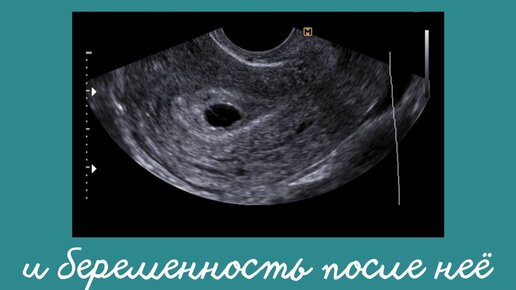

Пустое плодное яйцо, «замершая беременность» или анэбриония: из-за чего происходит, может ли быть ошибочным диагноз?

В ранние сроки гестации при подтверждении беременности может звучать диагноз анэмбриония, чем он опасен и что нужно делать, лечится ли это? Наступление беременности не всегда означает в дальнейшем появление на свет малыша, в некоторых случаях беременность может завершиться прерыванием или самопроизвольным выкидышем в силу различных причин. Многим женщинам знаком диагноз «замершая беременность» или отсутствие эмбриона в области плодного яйца – анэмбриония. Подобное состояние – это всегда шок и стресс...

О таком состоянии говорят врачи, когда во время уже наступившей беременности по данным УЗИ в плодном яйце отсутствует эмбрион. Почти в трети случаев наступившая беременность характеризуется данным состоянием, но обычно она прерывается на столь ранних сроках, что женщина о ней может и не узнать даже...